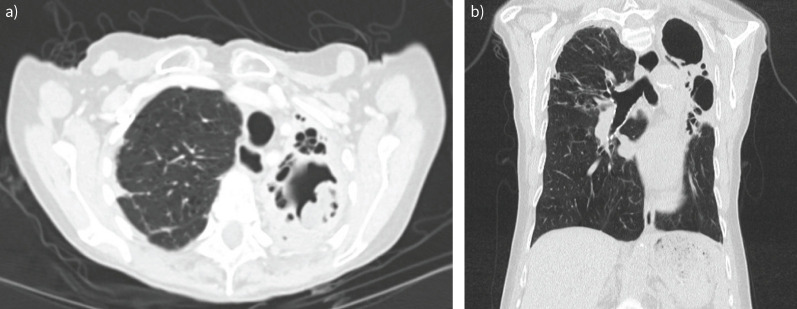

Chronic pulmonary aspergillosis has a range of manifestations from indolent nodules to semi-invasive infection. Patients may be asymptomatic or have chronic symptoms such as cough and weight loss or present with life-threatening haemoptysis. The physician can choose from a range of available therapies including medical therapy with antifungals, minimally invasive therapy with intracavitary antifungal therapy and surgery involving open thoracotomy or video-assisted thoracoscopic surgery. The patients with the most severe forms of pulmonary infection may not be surgical candidates due to their underlying pulmonary condition. The management of haemoptysis can include tranexamic acid, bronchial artery embolisation, antifungals or surgery. There are few controlled studies to inform clinicians managing complex cases, so a multidisciplinary approach may be helpful.